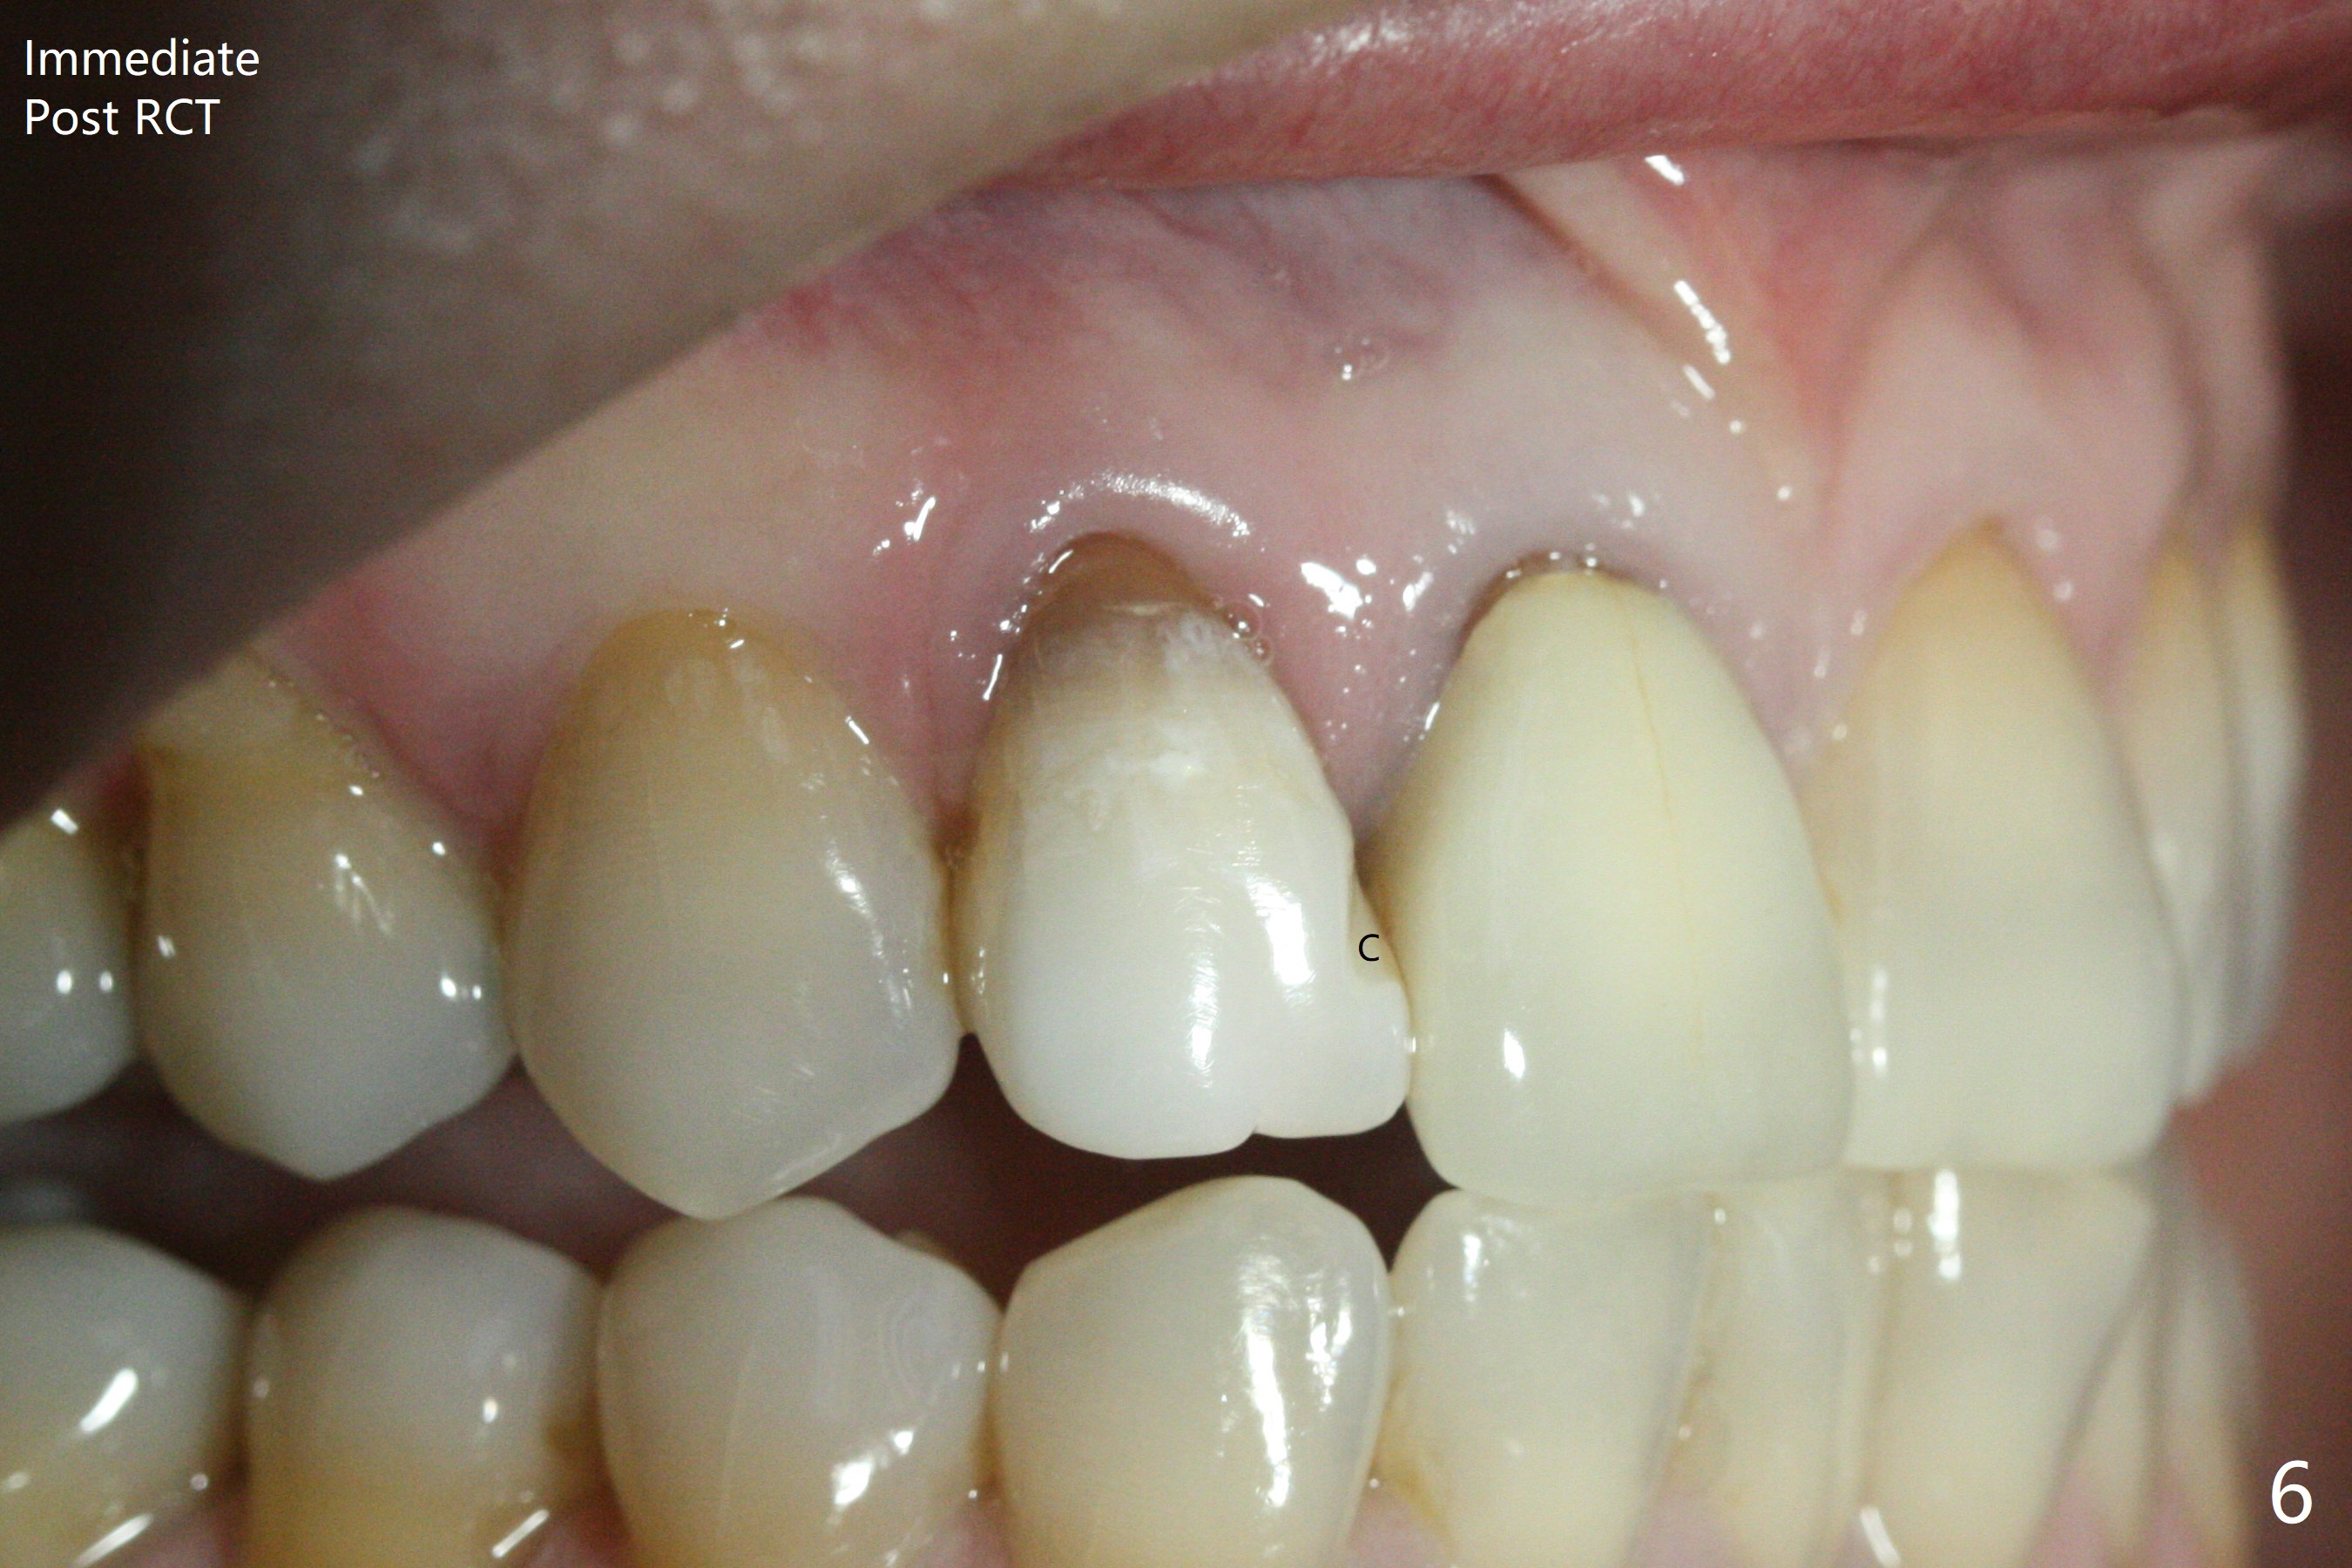

A 46-year-old woman requests a crown for the discolored tooth #7 (Fig.1,2) with mesiolingual composite (Fig.3 C) and periapical radiolucency (*). After RCT (Fig.4,5) with sodium hypochlorite, the tooth #7 is whiter than the ML composite (Fig.6,7). The patient returns 1 day post RCT for in house internal and external bleaching (Fig.8) with 35% hydrogen peroxide gel closed in the canal when she leaves. Three weeks later, the lateral incisor has the shade as the neighboring natural teeth (Fig.9,10). After the lightest shade composite placed in the canal and the access hole (Fig.11), the lateral looks better than the central with a crown and cervical discoloration (Fig.12).